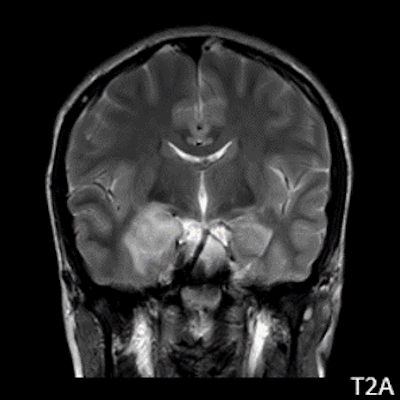

- A) Sağ temporal lob anteromedialinde silik sınırlı BT’de hipodens (ok), MRG’de T2AG ve FLAIR hiperintens (oklar), T1AG izo-hipointens (ok) sinyal özelliğinde ekspansil kitlesel lezyon izlenmektedir.

- MRG: T1A serilerde solid komponent izo-hipointens, T2A serilerde genellikle hiperintens sinyalde görülür. Peritümöral T2/FLAIR hiperintens kitle ödemi oldukça nadirdir. T1 C+ görüntülerde solid komponentte değişken oranda kontrastlanma ,T2*(SWI) serilerde eğer kalsifikasyon eşlik etmekteyse buna bağlı blooming artefaktları görülebilir.